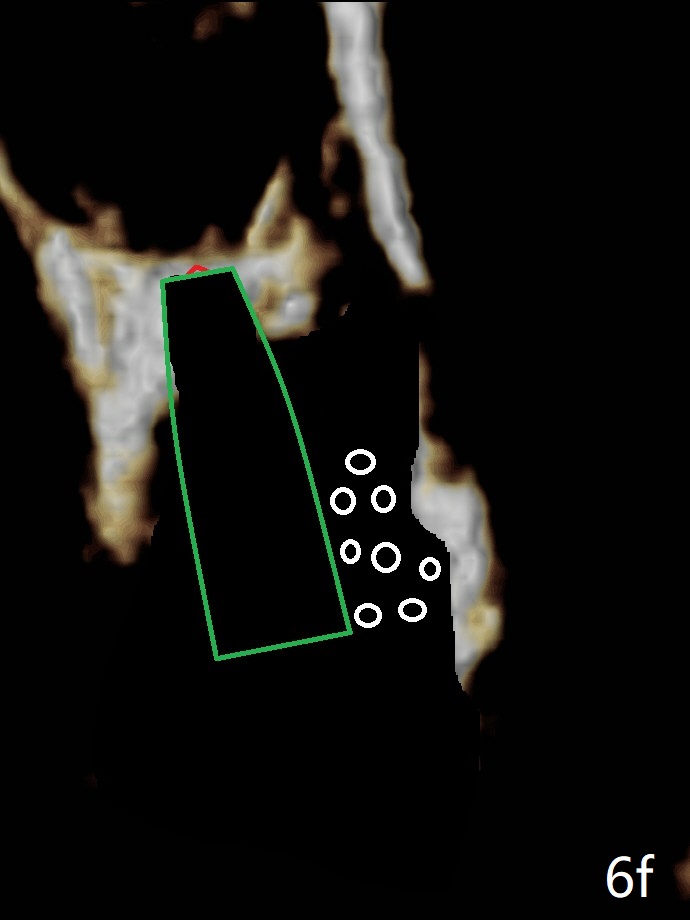

If the implant were placed first, the access to the buccal apical area (Fig.6e: *) would be smaller than when the last drill is in place.  Bone graft may be not placed deep enough (Fig.6f).